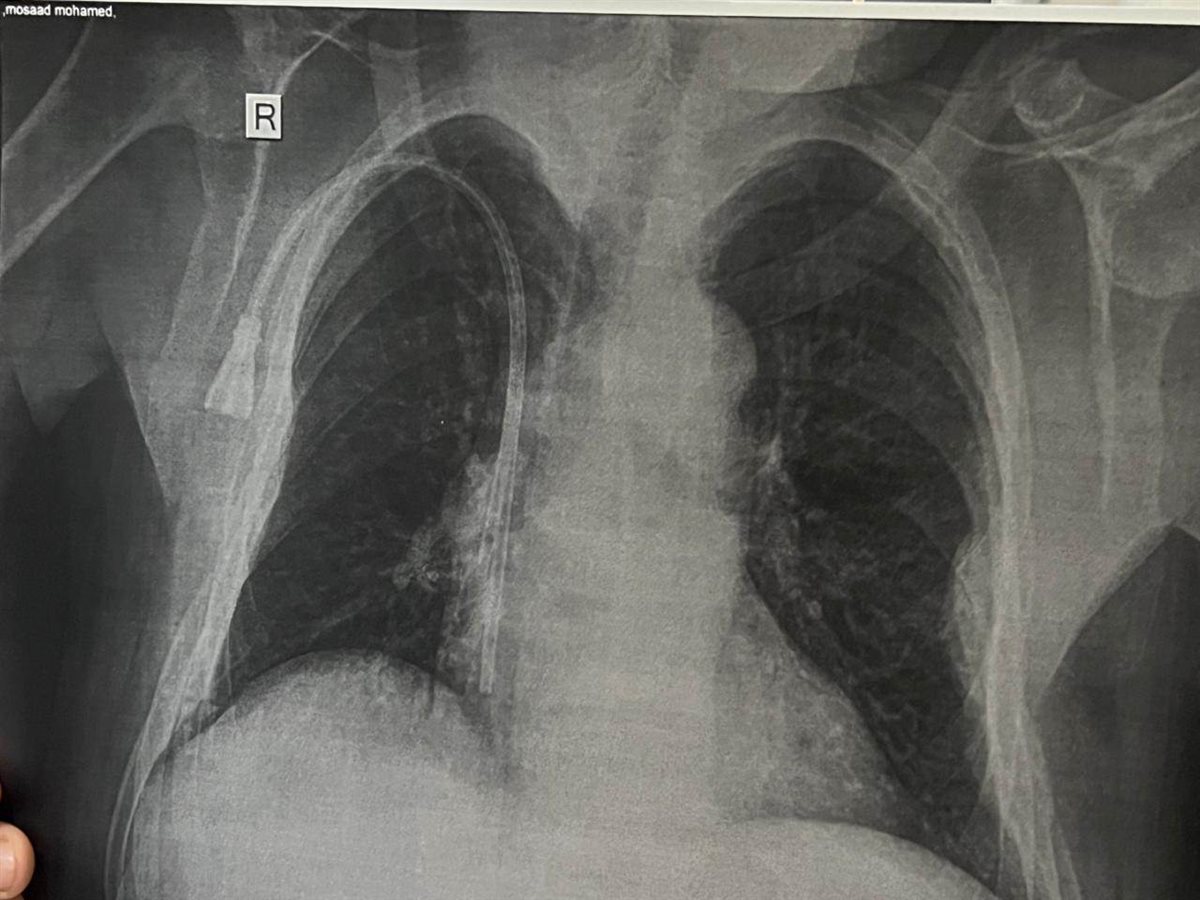

وفى هذا الصدد نجح أطباء قسم الكلي بمستشفي المحموديه المركزي فى اجراء عدة عمليات جراحية حرجة لتركيب 2 قسطرة مستديمة عنقية ، و3 قساطر مؤقته عنقية ، و2قسطره مؤقته فخذية لعدد من المرضي الذين يعانون من الفشل الكلوي المزمن والمترددين علي قسم الغسيل الكلوي وذلك لتخفيف العبء عن كاهل مرضي الغسيل الكلوي بمركز المحموديه